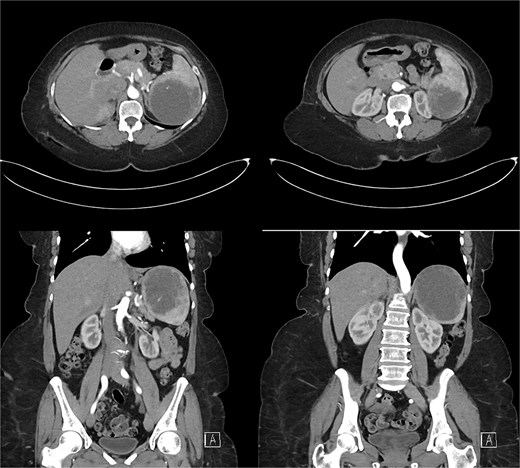

Laboratory results were within normal limits (hemoglobin 120 g/l, WBC 4.72 × 109/l). Abdominal ultrasound showed a well-defined multilocular cystic lesion with internal echoes in the spleen, measuring 7.9 × 6.9 cm, with possible hematoma (Fig. 1). No significant free fluid was detected. A CT scan revealed a large, non-enhancing hypodense splenic cyst with internal septations, calcifications, and multiple peripheral daughter cysts (Fig. 2). The splenic hilum and capsule were intact, with no perisplenic fat stranding. The main differential diagnosis was a type II hydatid cyst. No solid organ injury or significant free fluid was observed.

Abdominal and pelvic CT scan revealed a large, non-enhancing hypodense cystic lesion in the spleen with internal septations, calcifications, and multiple smaller daughter cysts arranged peripherally. Prime differential was type II hydatid cyst.